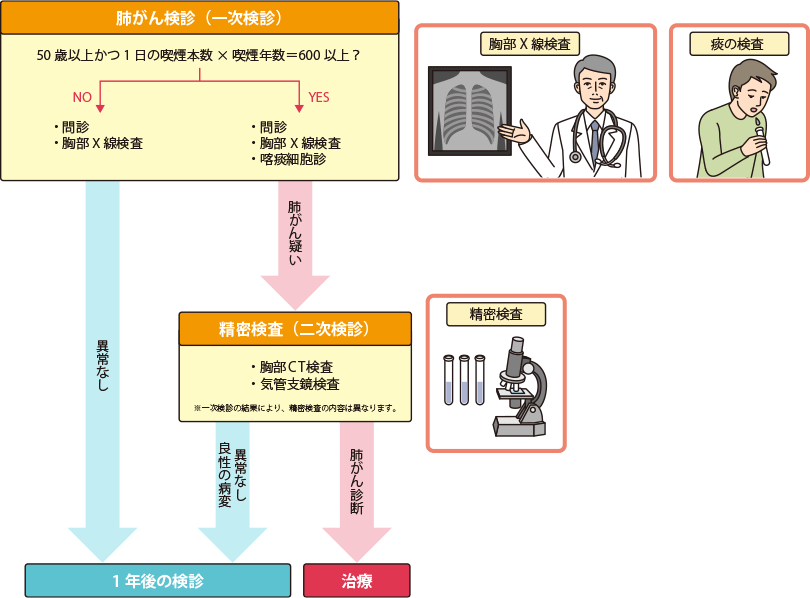

胸部X線検査、喫煙者では喀痰検査も

肺がん検診では、胸部X線検査(レントゲン検査)を行います。これは、肺全体のレントゲン画像を撮る方法です。タバコをたくさん吸うなど肺がんになるリスクの高い人は、レントゲン検査に加えて、喀痰細胞診を行います。

喀痰細胞診とは、痰を採取して、痰に混じっているがん細胞があるかどうかを顕微鏡で観察する方法です。喫煙者に多いとされる、気管支の太い部分にできる扁平上皮癌は、この検査で見つかる可能性があります。喀痰細胞診の検査対象となるのは、50歳以上で、喫煙指数(1日の喫煙本数×喫煙年数)が600以上の人と定められています。現在たばこを吸っている人だけでなく、過去にたばこを吸っていた人も対象となります。喀痰細胞診は、必ずレントゲン検査と一緒に行われます。

肺がん検診の流れ

精密検査が必要と言われたら?

肺がん検診で、「がんの疑いがあります」「精密検査を受けてください」などと言われた場合は、そのまま放置せずに、なるべく早く医療機関で精密検査(さらに詳しく行う検査)を受けましょう。

精密検査では、胸部CT検査や、気管支鏡検査などを行います。気管支鏡検査とは、口から気管支に内視鏡を入れて、がんができている可能性のある部位を直接観察する方法です。必要に応じて、その部位の細胞を採取して、悪性の腫瘍かどうかを診断します。

精密検査の方法は、「がんができているかもしれない場所」や、「できているものが悪性の可能性が高いかどうか」など、ひとりひとりの状態によって決められます。